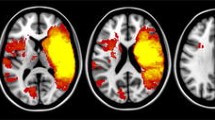

The completion times for the TMTA and TMTB were associated with a very large number of structures (Fig. 3a; Table 2; Supplement Table 3); the latter were characterized by slight overall right prominence (52.7% of the significant voxels) for the TMTA and left prominence for the TMTB (64.7% of the significant voxels). The TMTA and TMTB both involved regions underlying visual-spatial processing (the occipital, temporal and parietal lobes, the optic radiations and their connections, including the inferior longitudinal fasciculus (ILF) and the inferior occipitofrontal fasciculus (IOFF)), the motor system (precentral, corticospinal, and internal capsule), the frontal lobes (three frontal lateral gyri and, for the TMTB, the dorsomedial area) and their subcortical connections (the frontostriatal and thalamofrontal tracts).

A VLSM analysis of demographically adjusted scores (left-side structures are shown on the left of the figure). 3a (upper). The completion times in the TMTA (in blue) and TMTB (in red) (overlapping in purple). 3b (lower). Semantic fluency (in blue) and phonemic fluency (in red) (overlapping in purple). TMT Trail Making Test